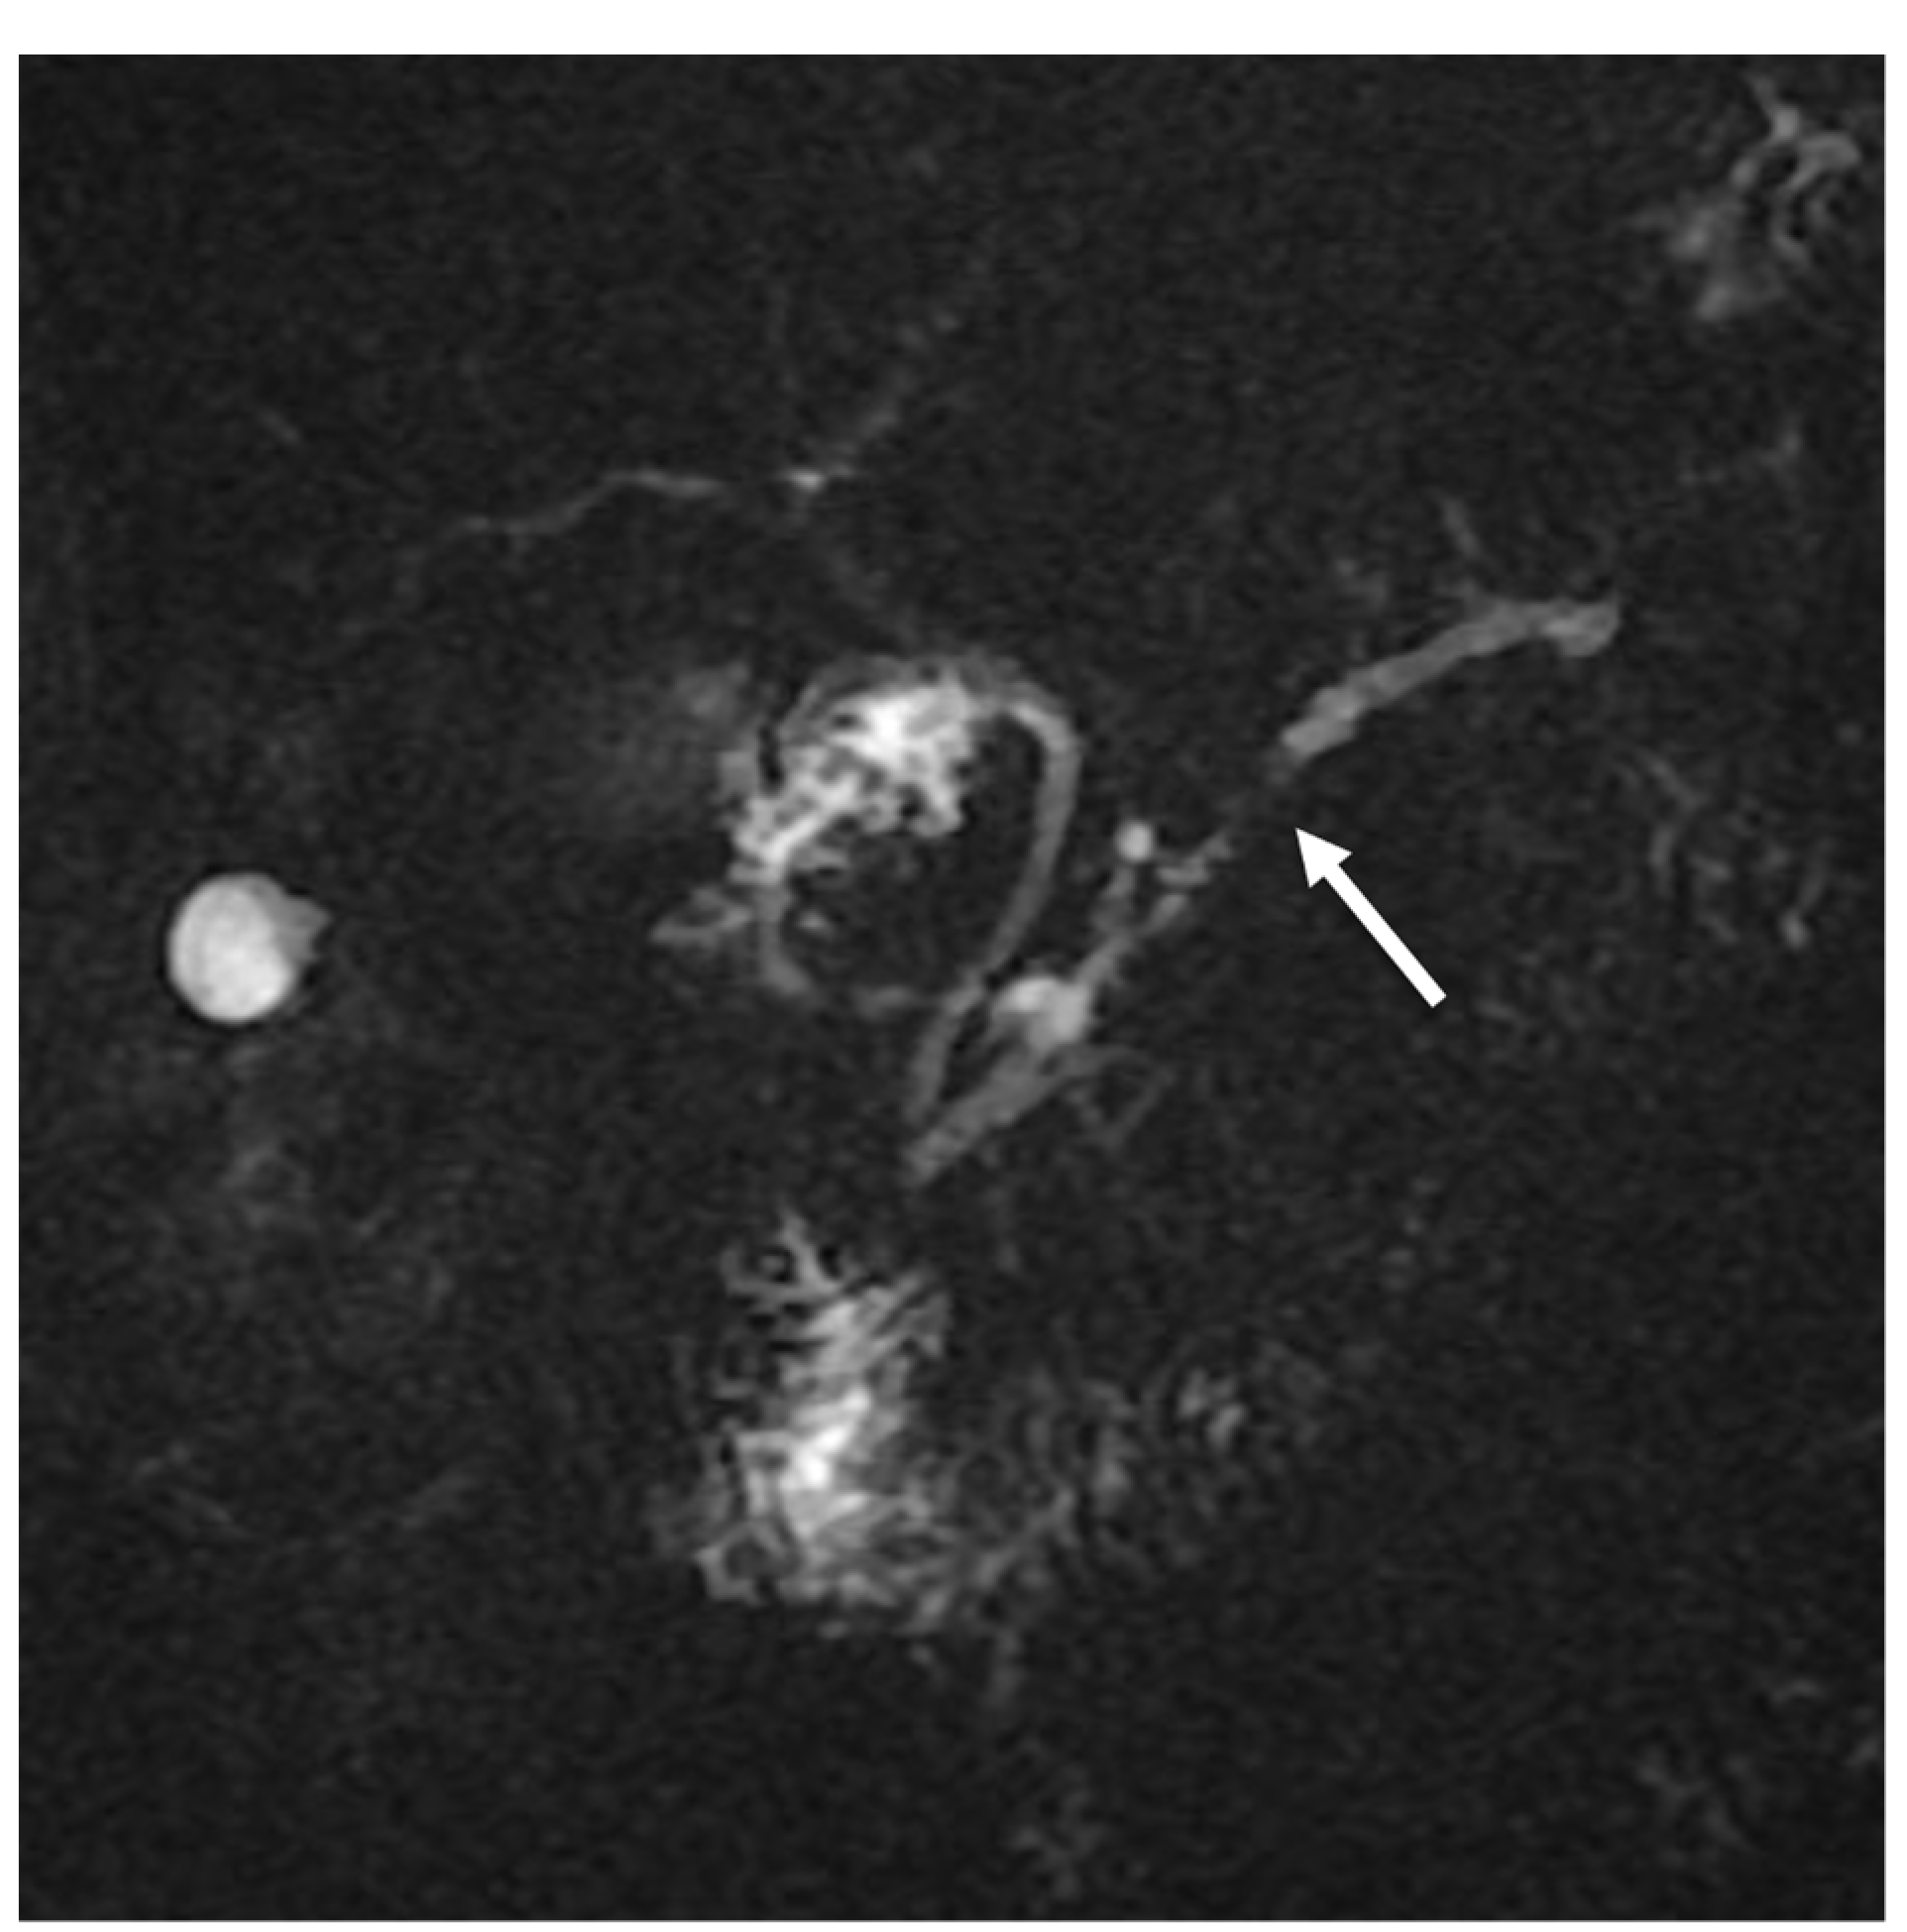

2. Case Report